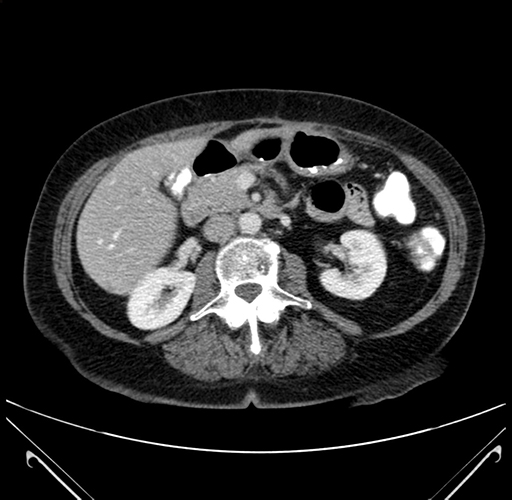

Pre-Chemo: Axial Venous

Axial Venous